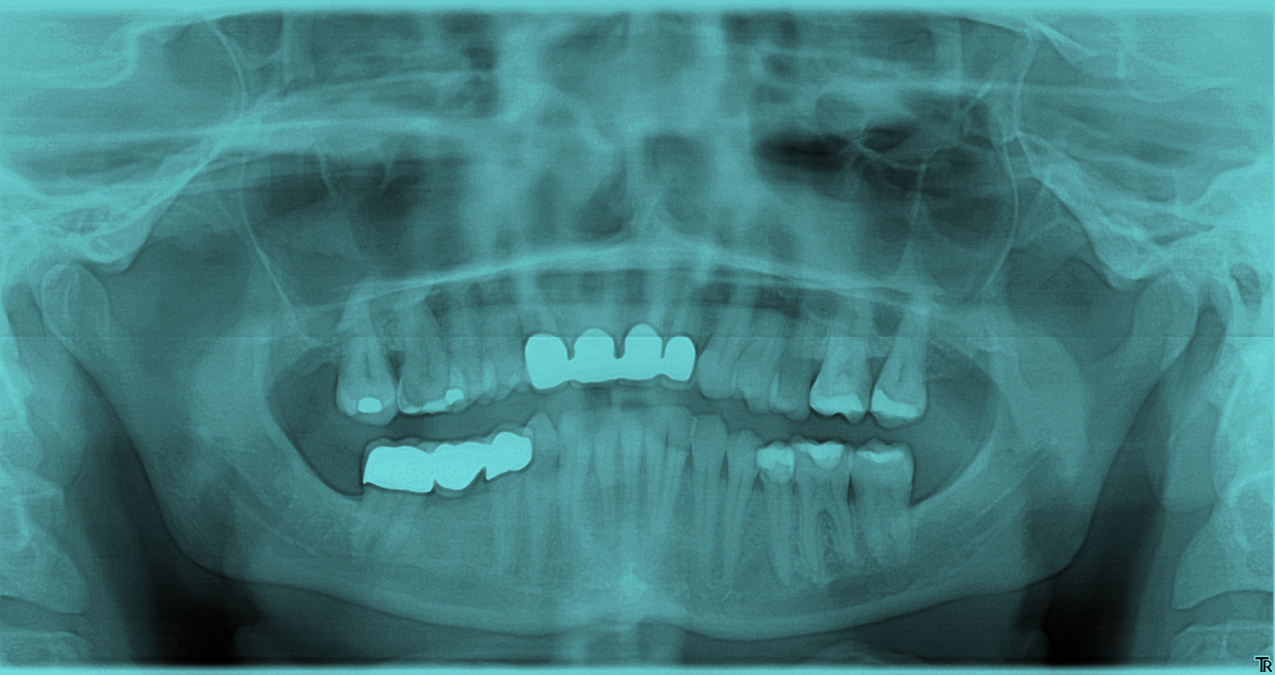

How Does TMJ Cause Ear Pain Konig Center for Cosmetic & Comprehensive Dentistry